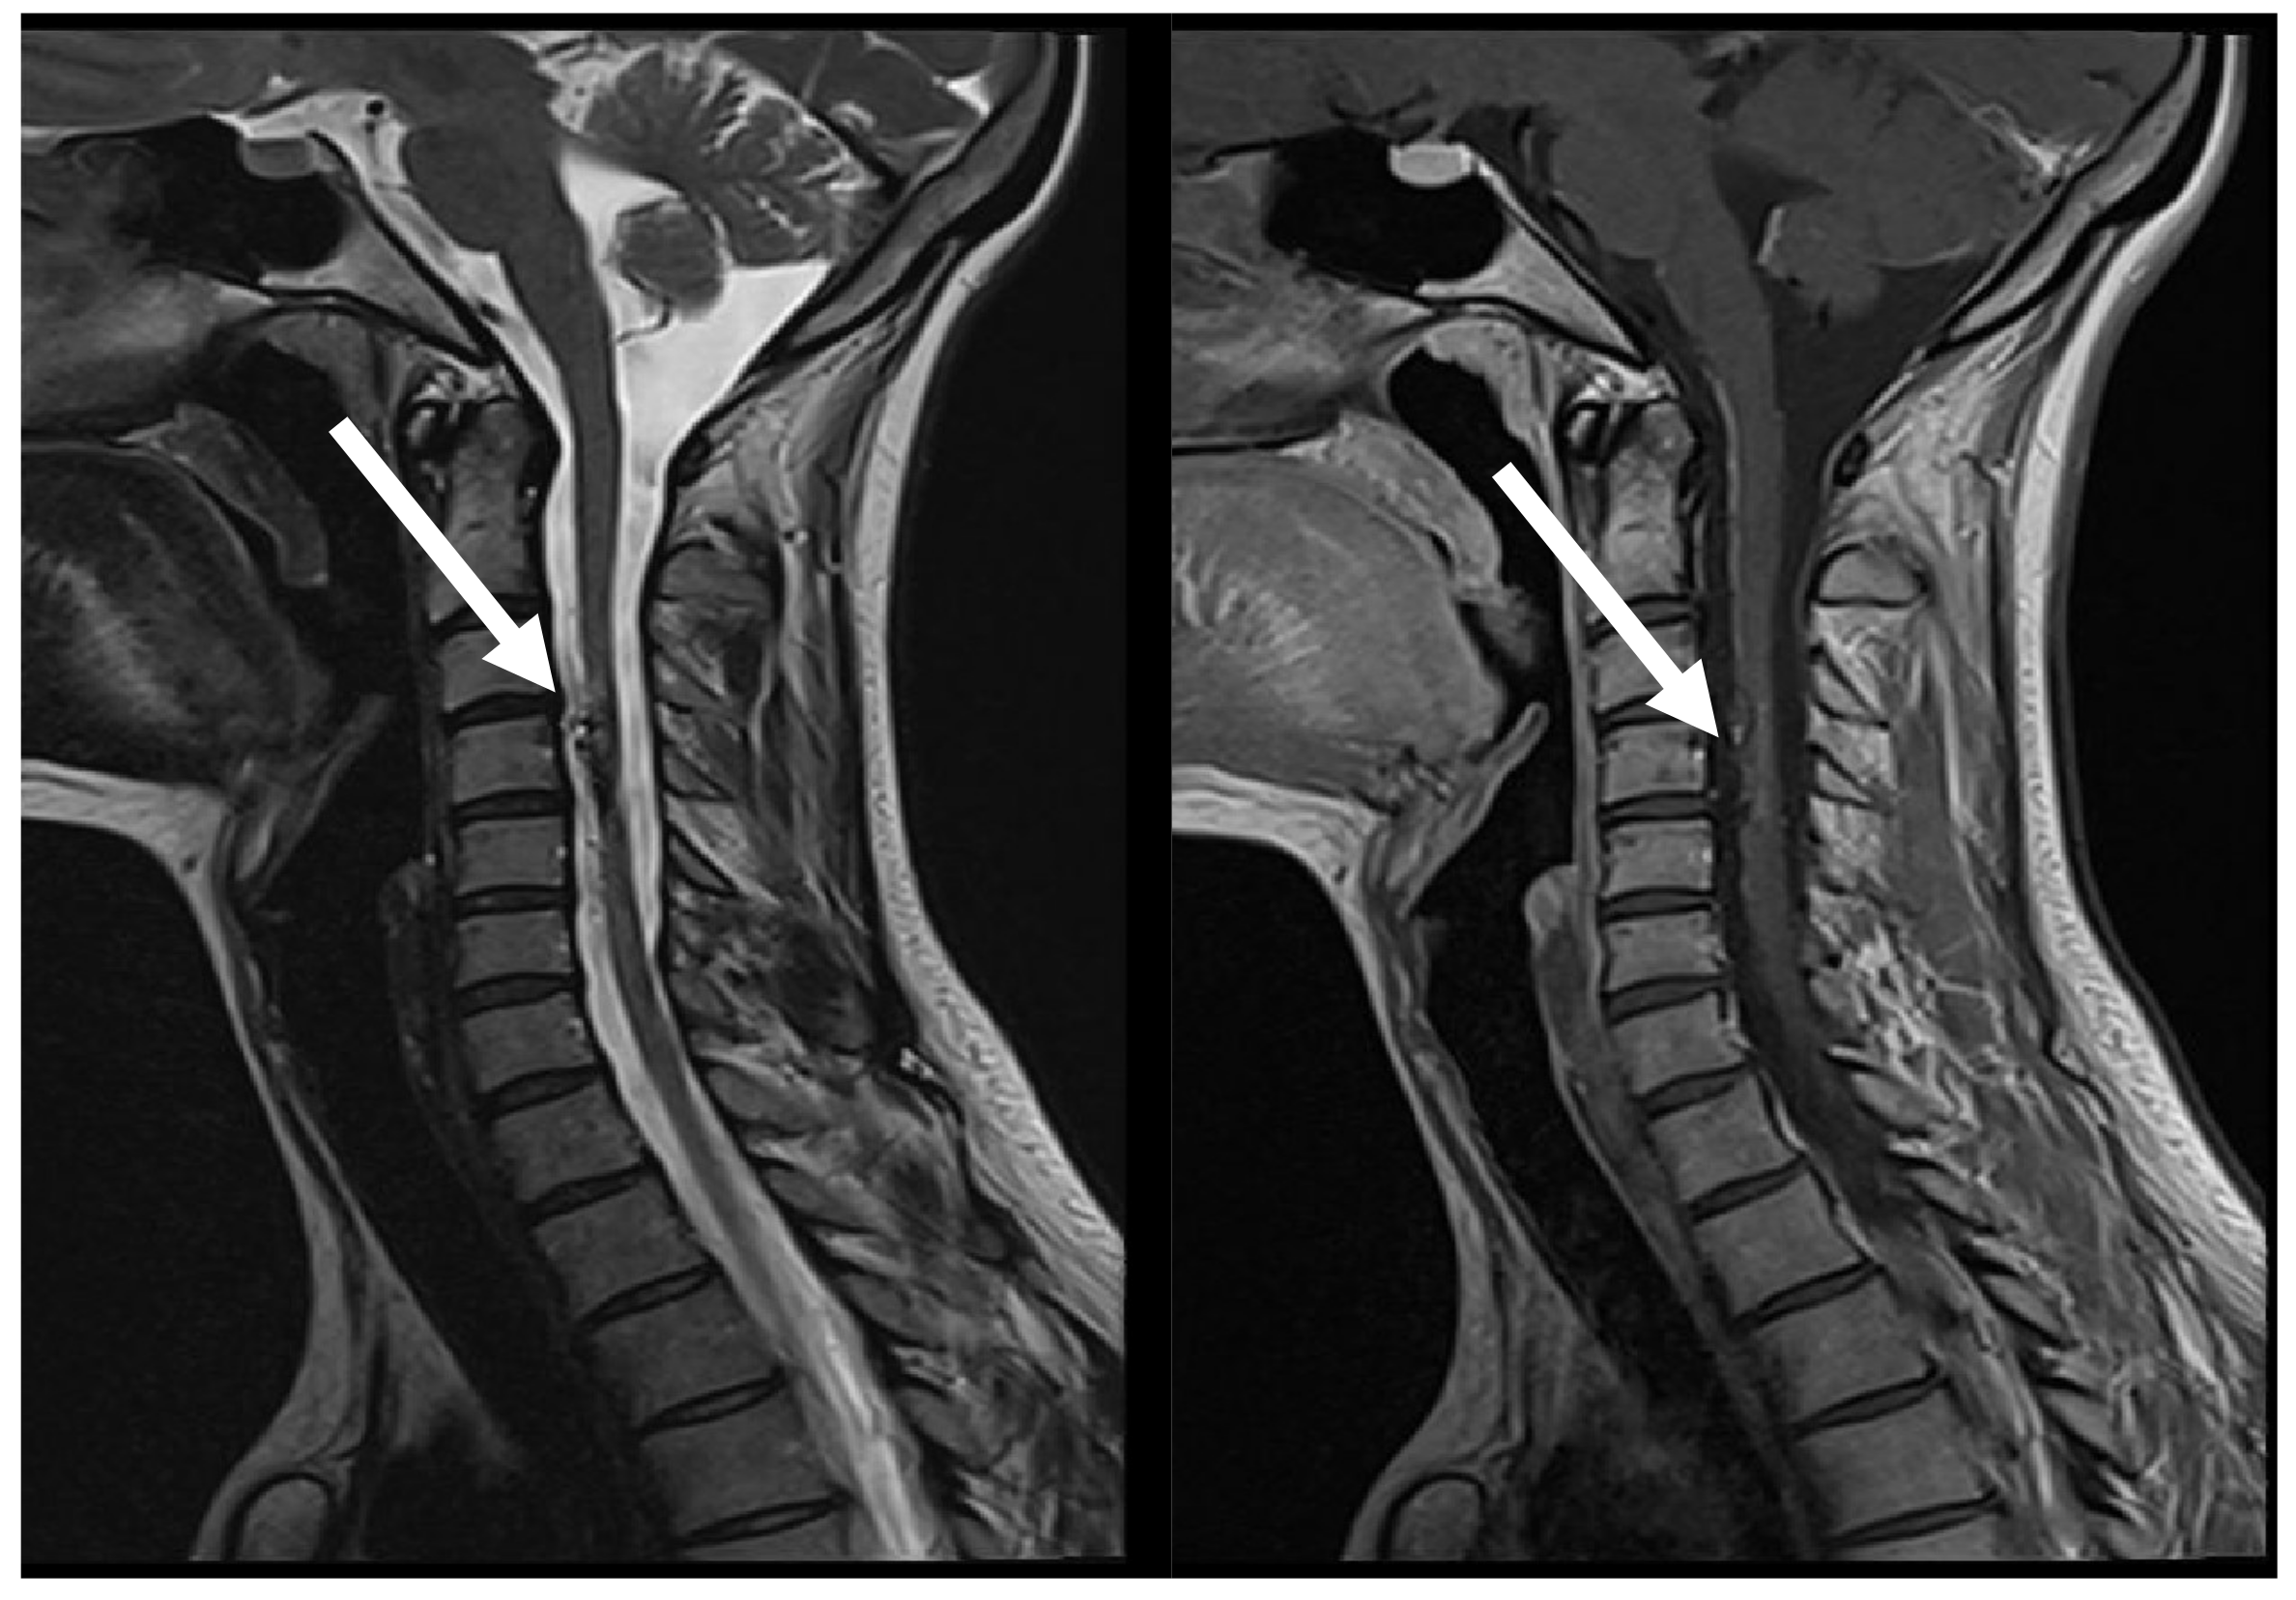

7.3. Third Episode (2023)